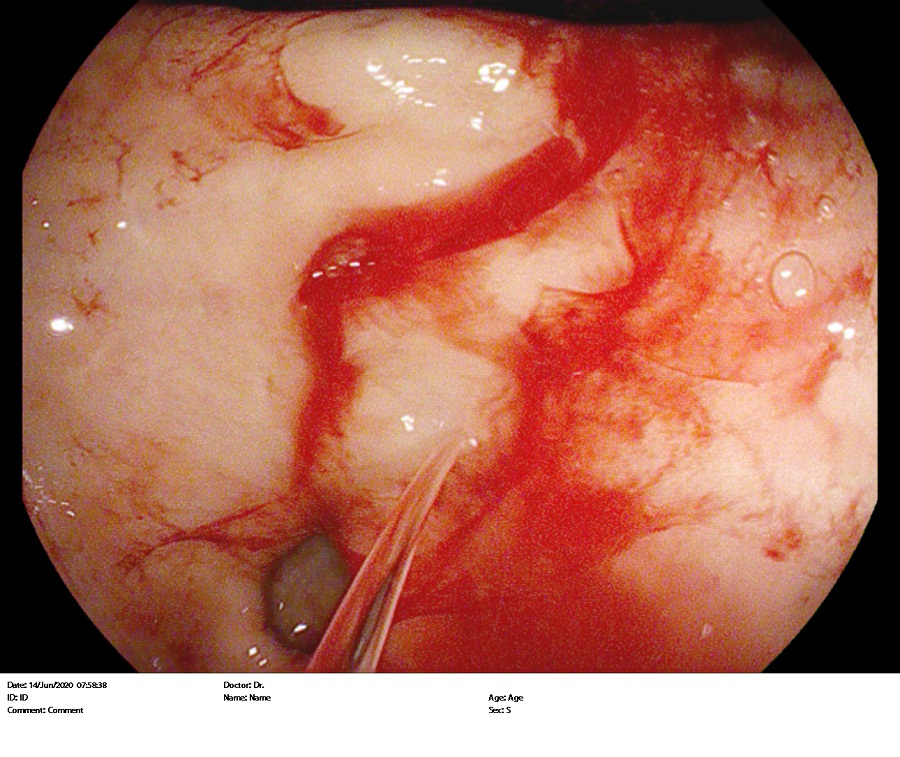

消化内分泌科胃肠镜室于6月1日及6月14日完成2例杜氏病十二指肠降部出血内镜下止血术。

杜氏病是胃粘膜下恒径动脉畸形引起的出血,是一种较少见得引起消化道出血的病因。

其中患者为老年男性,57岁,缘于入院前一天无明显诱因出现反复黑便于5月31日急来我院在消化内科住院,入院血常规血色素为100g/L,给予止血、补液对症治疗无效,出血仍然不止,血常规血色素下降到68 g/L,于6月1日在胃镜室行急诊胃镜,发现患者胃底、胃体、胃窦部大量新鲜出血附着影响观察,继续进镜发现十二指肠球部新鲜出血附着,十二指肠降部见新鲜出血点,呈波动性喷射状,考虑为杜式病引起的十二指肠降部出血,立即给予钛夹钳夹止血,出血停止,给予2单位去白悬浮红细胞,于6月3日复查血常规血色素为78 g/L,于6月6日再次复查血常规血色素为79 g/L,内镜下止血后患者未再呕血及黑便,出血完全止住,准备出院。追问患者病史,患者1年前也因十二指肠出血在承德市中心医院给予钛夹钳夹止血。另1例患者为ICU患者,患者反复呕血、便血15个小时,共输血10U去白悬浮红细胞,1500ml血浆,血色素仍然继续下降,内科保守治疗效果欠佳,仍然出血不止,患者烦躁,生命体征不平稳,在气管插管静脉麻醉下给予内镜下止血治疗后血色素上升,未再呕血,此次内镜下止血为我院完成的杜式病引起出血内镜下止血首例,填补了我院此项技术的空白,同时为患者减少了住院日、减轻治疗花销,同时也避免了转院,给患者带来了福音。